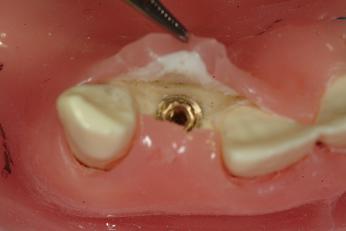

二次手術

局所麻酔下(ご希望の場合には鎮静状態での治療(点滴麻酔))に行います。

埋入したインプラントの頭の部分の歯茎をレーザーでカットし、頭出しを行います。インプラントにヒーリングアバットメントという歯肉を適正な形態に整える支柱を装着します。

この状態で歯肉形態が安定するまで1~4週間ほど置きます。場合によってはこの時に仮歯を装着する治療を行うこともあります。